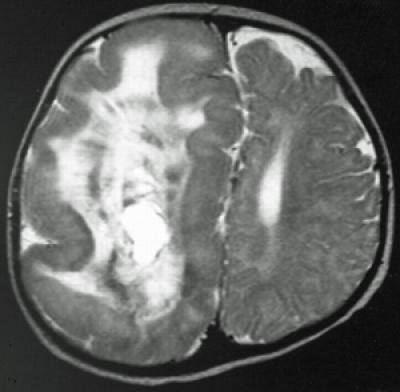

image: This image depicts hemimegalencephaly. view more

Hemimegalencephaly is a rare but dramatic condition in which the brain grows asymmetrically, with one hemisphere becoming massively enlarged. Though frequently diagnosed in children with severe epilepsy, the cause of hemimegalencephaly is unknown and current treatment is radical: surgical removal of some or all of the diseased half of the brain.